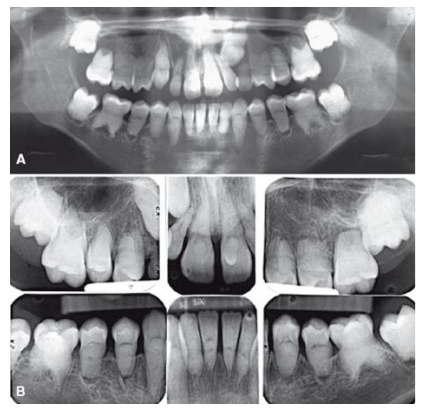

As imagens radiográficas extraoral (A) e intraoral (B) mostram raízes curtas e pouco desenvolvidas,

câmaras pulpares e canais radiculares obliterados, além de osteíte periapical rarefaciente associada.

Observe a meia-lua ou a forma “semilunar” das câmaras pulpares.